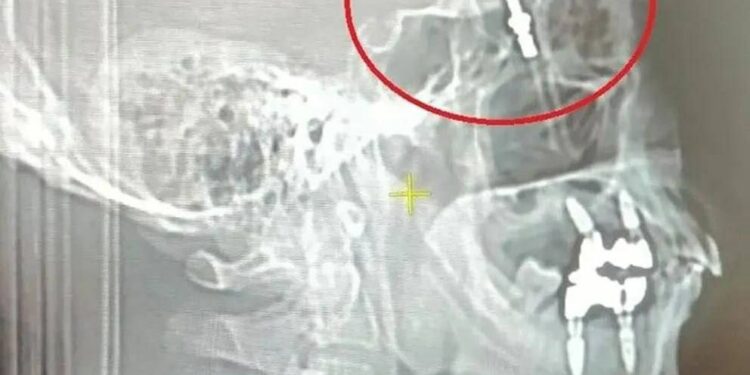

Бейтап макул болгон соң, дарыгер тишти колу менен орното баштаган. Тиш доктур имплантты ушунчалык күч менен бурап салгандыктан, темир баш сөөктүн сөөктөрүн сындырып, мээге тийген. Бир убакта Йылмаз качыраган үндү угуп, анан катуу ооруну сезген.

«Дарыгер тишти орнотууга аракет кылганда, анын ашыкча күч колдонуп жатканын байкадым. Мен ага сөөктүн сынганына окшош үн уктум деп айттым. Бирок ал ошондой эле болорун айтты», — деген бейтап.